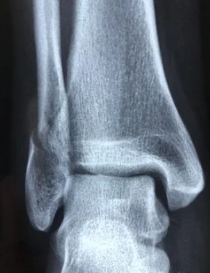

발등을 다치는것은 보통 넘어지거나 운동을 하다가 다치는 일이 많은데요. 발등 인대가 늘어났을때 한동안 걷는것도 힘들다가 서서히 나으면서 운동하거나 걷는데 무리가 없게 됩니다. 하지만 순간적으로 발에 힘을 주거나 발목을 돌릴때는 통증이 꽤 오래 갑니다.

발등인대가 늘어나면 치료기간은 보통 3개월 이상 걸리는데요. 발등 인대는 한번 다치면 몇년이 지나도 순간적인 통증이 계속해서 나타나게 된답니다. 때문에 물리치료를 받고 치료를 하더라도 절대 다 나았다는 생각은 금물이고 완전히 치료하기까지 운동도 해서는 안됩니다.

발등 인대 늘어났을때는 바로 얼음찜질을 하셔야 하고요. 무조건 2주이상 발목을 최대한 쉬게 하셔야 합니다. 인대가 늘어나면 아예 걷는것조차 힘들고 못움직이게 되는데요. 보험들었다면 실비청구하시면 보장받을 수 있으시고 병원은 한의원 가시거나 정형외과를 가시면 됩니다. 이럴때를 대비해서 꼭 보험은 꼭 필요한것 같아요.